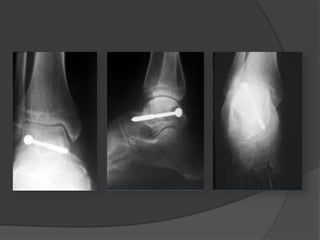

TRATAMIENTO

 Abordajes – anteromedial

- anterolateral

- posterolateral

 Osteotomía maleolar interna

POSTOPERATORIO

 No apoyo por 10-12 sem

 Movilizacion temprana a tolerancia.

 Apoyo al encontrar consolidacion radiologica

(hasta 4 meses).